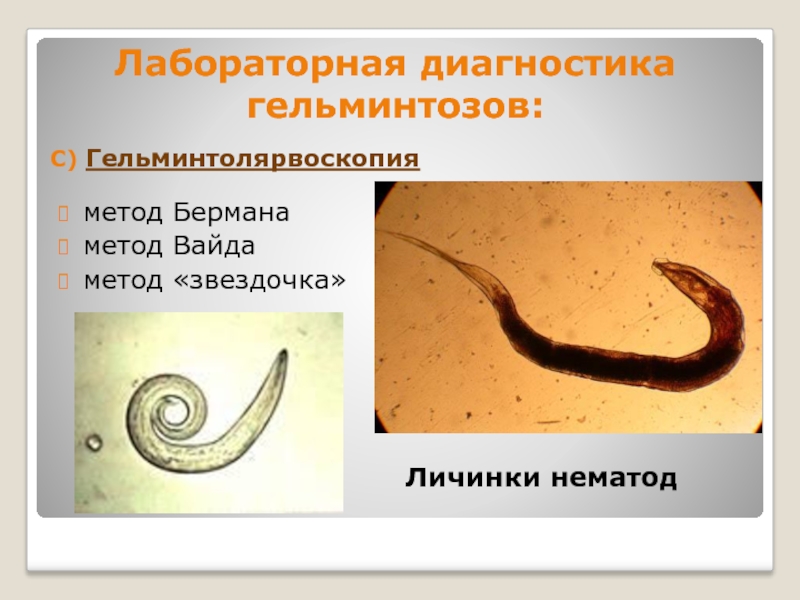

Фотографии нематод, цестод и трематод в природе